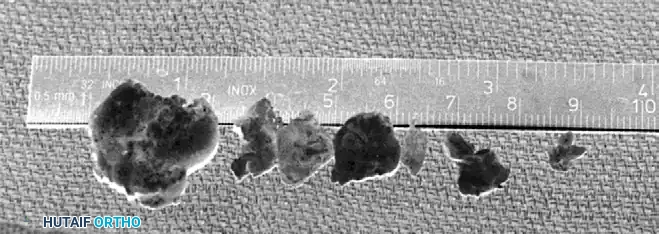

- Small Fragments: Removed via standard arthroscopic graspers through the working cannula.

- Large Fragments: Occasionally, loose bodies are too large to be extracted through a standard arthroscopic portal. These can be fragmented using an arthroscopic burr and removed piecemeal.

- Kocher Clamp Technique: Alternatively, large bodies can be left in place until the conclusion of the intra-articular work. They are then removed by longitudinally extending the capsular incision and extracting the intact fragment with a Kocher clamp. This delayed extraction prevents premature fluid extravasation into the anterior soft tissues, thereby decreasing the risk of neurovascular compromise during the remainder of the procedure.